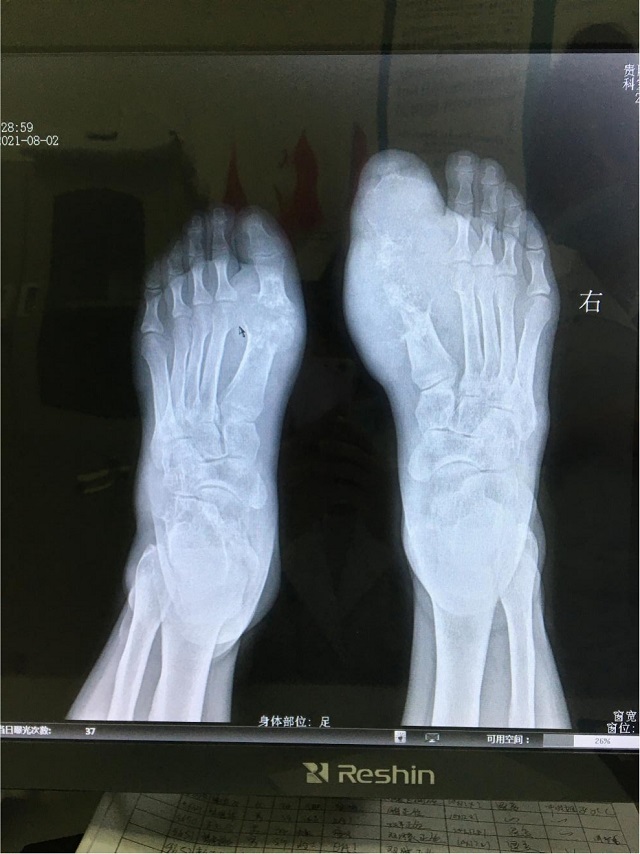

不愛吃海鮮,也很少喝酒,基本上不喝碳酸飲料,父母都沒有痛風(fēng)病史,那小伙子的痛風(fēng)由何而來?交流會現(xiàn)場來了一位痛風(fēng)患者,朱紅梅主任向大家展示了這位患者手術(shù)的一些圖片,其中有一張就是小伙子在做水筋針治療時從關(guān)節(jié)腔里擠出來的像牙膏一樣的液狀痛風(fēng)石。

接診過程中朱紅梅主任了解后發(fā)現(xiàn),小伙子偏好的飲食是牛肉、豬肉、雞肉,雖然少吃海鮮,喝酒喝碳酸飲料較少,但較少運動,所以他的尿酸高主要與個人的體質(zhì)因素有關(guān),即內(nèi)源性的尿酸生成多,轉(zhuǎn)化、排泄少,導(dǎo)致大量痛風(fēng)結(jié)晶沉積。

通過痛風(fēng)石切除術(shù)、中醫(yī)微創(chuàng)可視針刀鏡關(guān)節(jié)清理術(shù)以及水筋針手術(shù)清理后,輔助一系列中醫(yī)特色理療,患者坐著輪椅來院,現(xiàn)在不僅雙足大腳趾得以保全,行動與正常人差別并不大,活動范圍改善了很多。小伙子為表示對朱院長的感謝,現(xiàn)場還向朱院長贈送了錦旗。